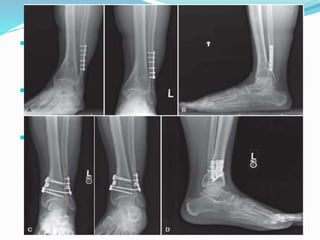

 Insert large, partially threaded, cannulated screws

(typically 6.5 to 8.0 mm) over guidewires .

 Three screws are ideal, but sometimes only two are

possible. The most desirable position is the so-called

“home run”. Screws positions are :

 1st screw : from the posterolateral tibia into the talar

neck/body

 2nd screw : proximomedial screw directed into the

posterior body of the talus

 3rd screw : proximal anterolateral to distal medial

screw or a distal lateral screw from the lateral process

of the talus directed proximal, posterior, and medial.